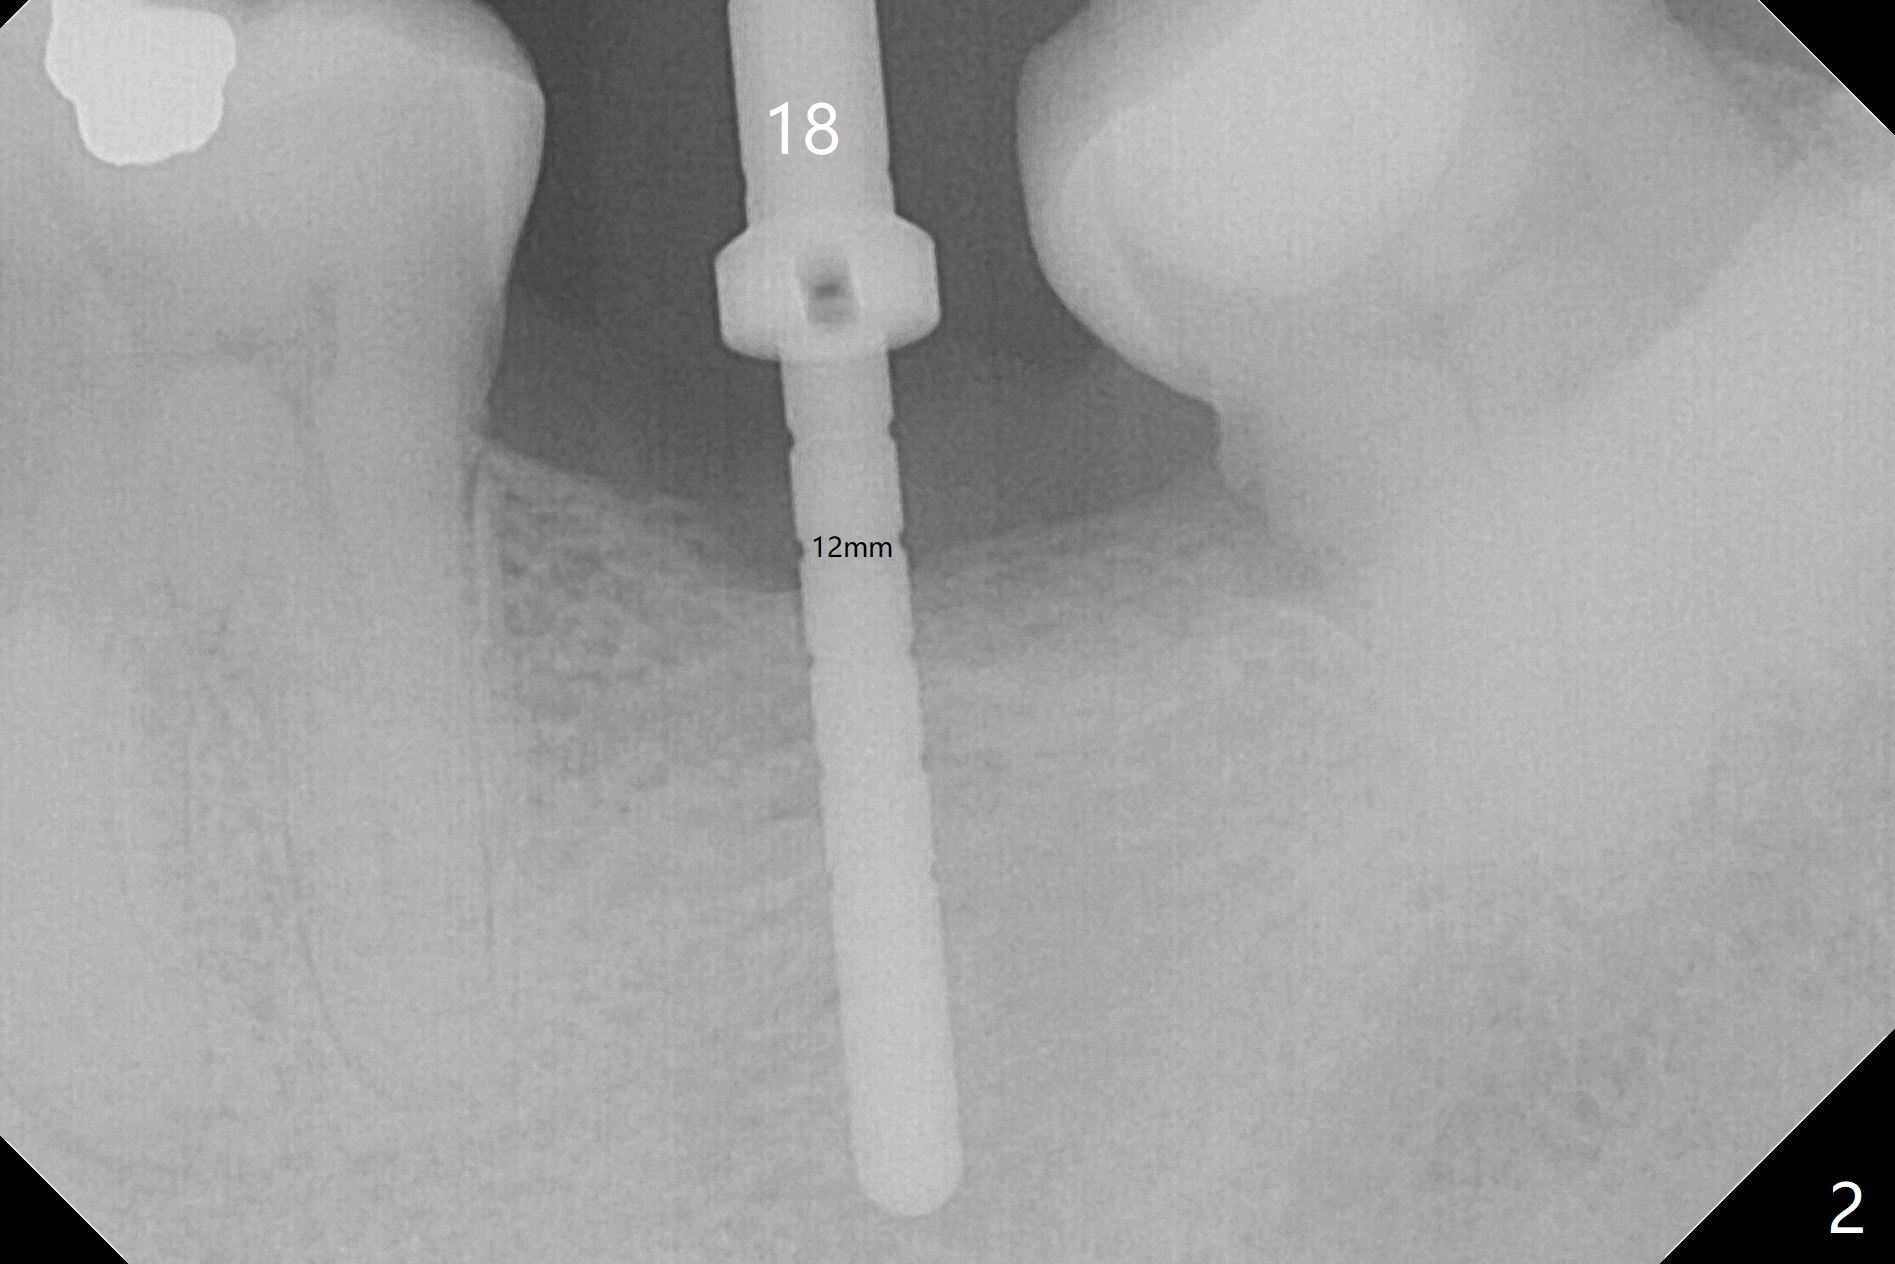

A 56-year-old man will return for #18 implant placement post 20, 14, and 29 ones. Considering postop bone loss associated with delayed implant, an implant (13 or 15 mm long) at #18 is to be placed subcrestal (Fig.1 (pan taken when the implant was placed at #20)).